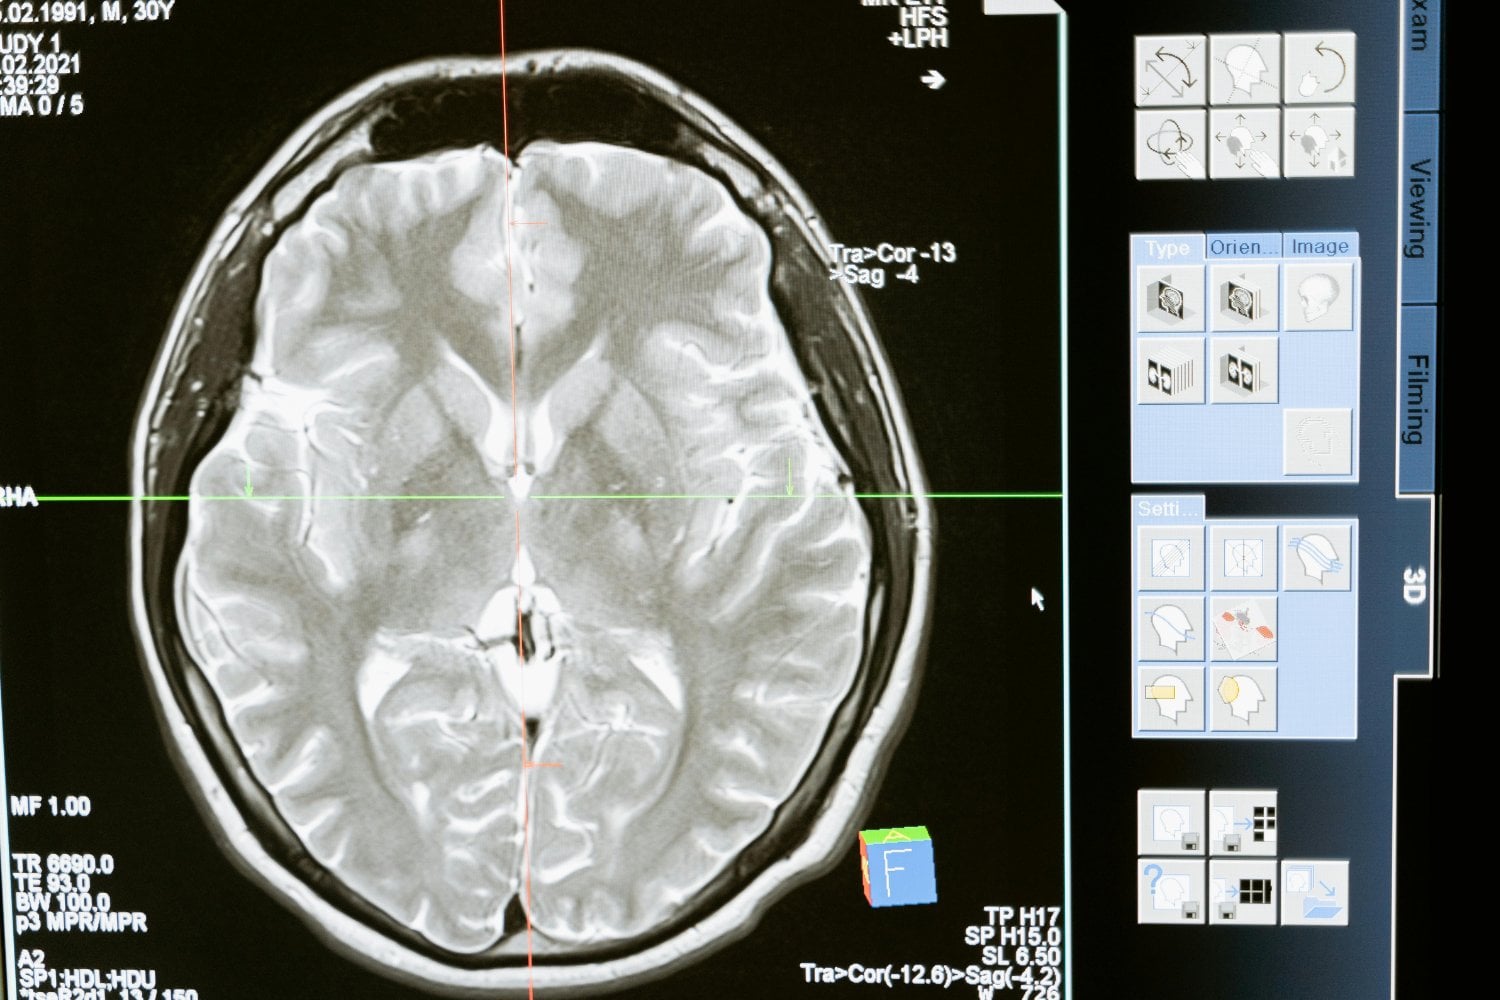

Uno de los hallazgos más debatidos surgió al estudiar la actividad cerebral durante el sueño. Mediante electroencefalografía, algunos investigadores detectaron actividad en regiones occipitales —normalmente asociadas a la visión— en personas ciegas de nacimiento.

Esto sugiere que el cerebro puede “reutilizar” áreas visuales para procesar información procedente de otros sentidos, como el oído o el tacto. En algunos experimentos, participantes ciegos describieron escenas y dibujaron figuras humanas tras despertar, aunque con características diferentes a las de los videntes, como una mayor presencia de rasgos auditivos.